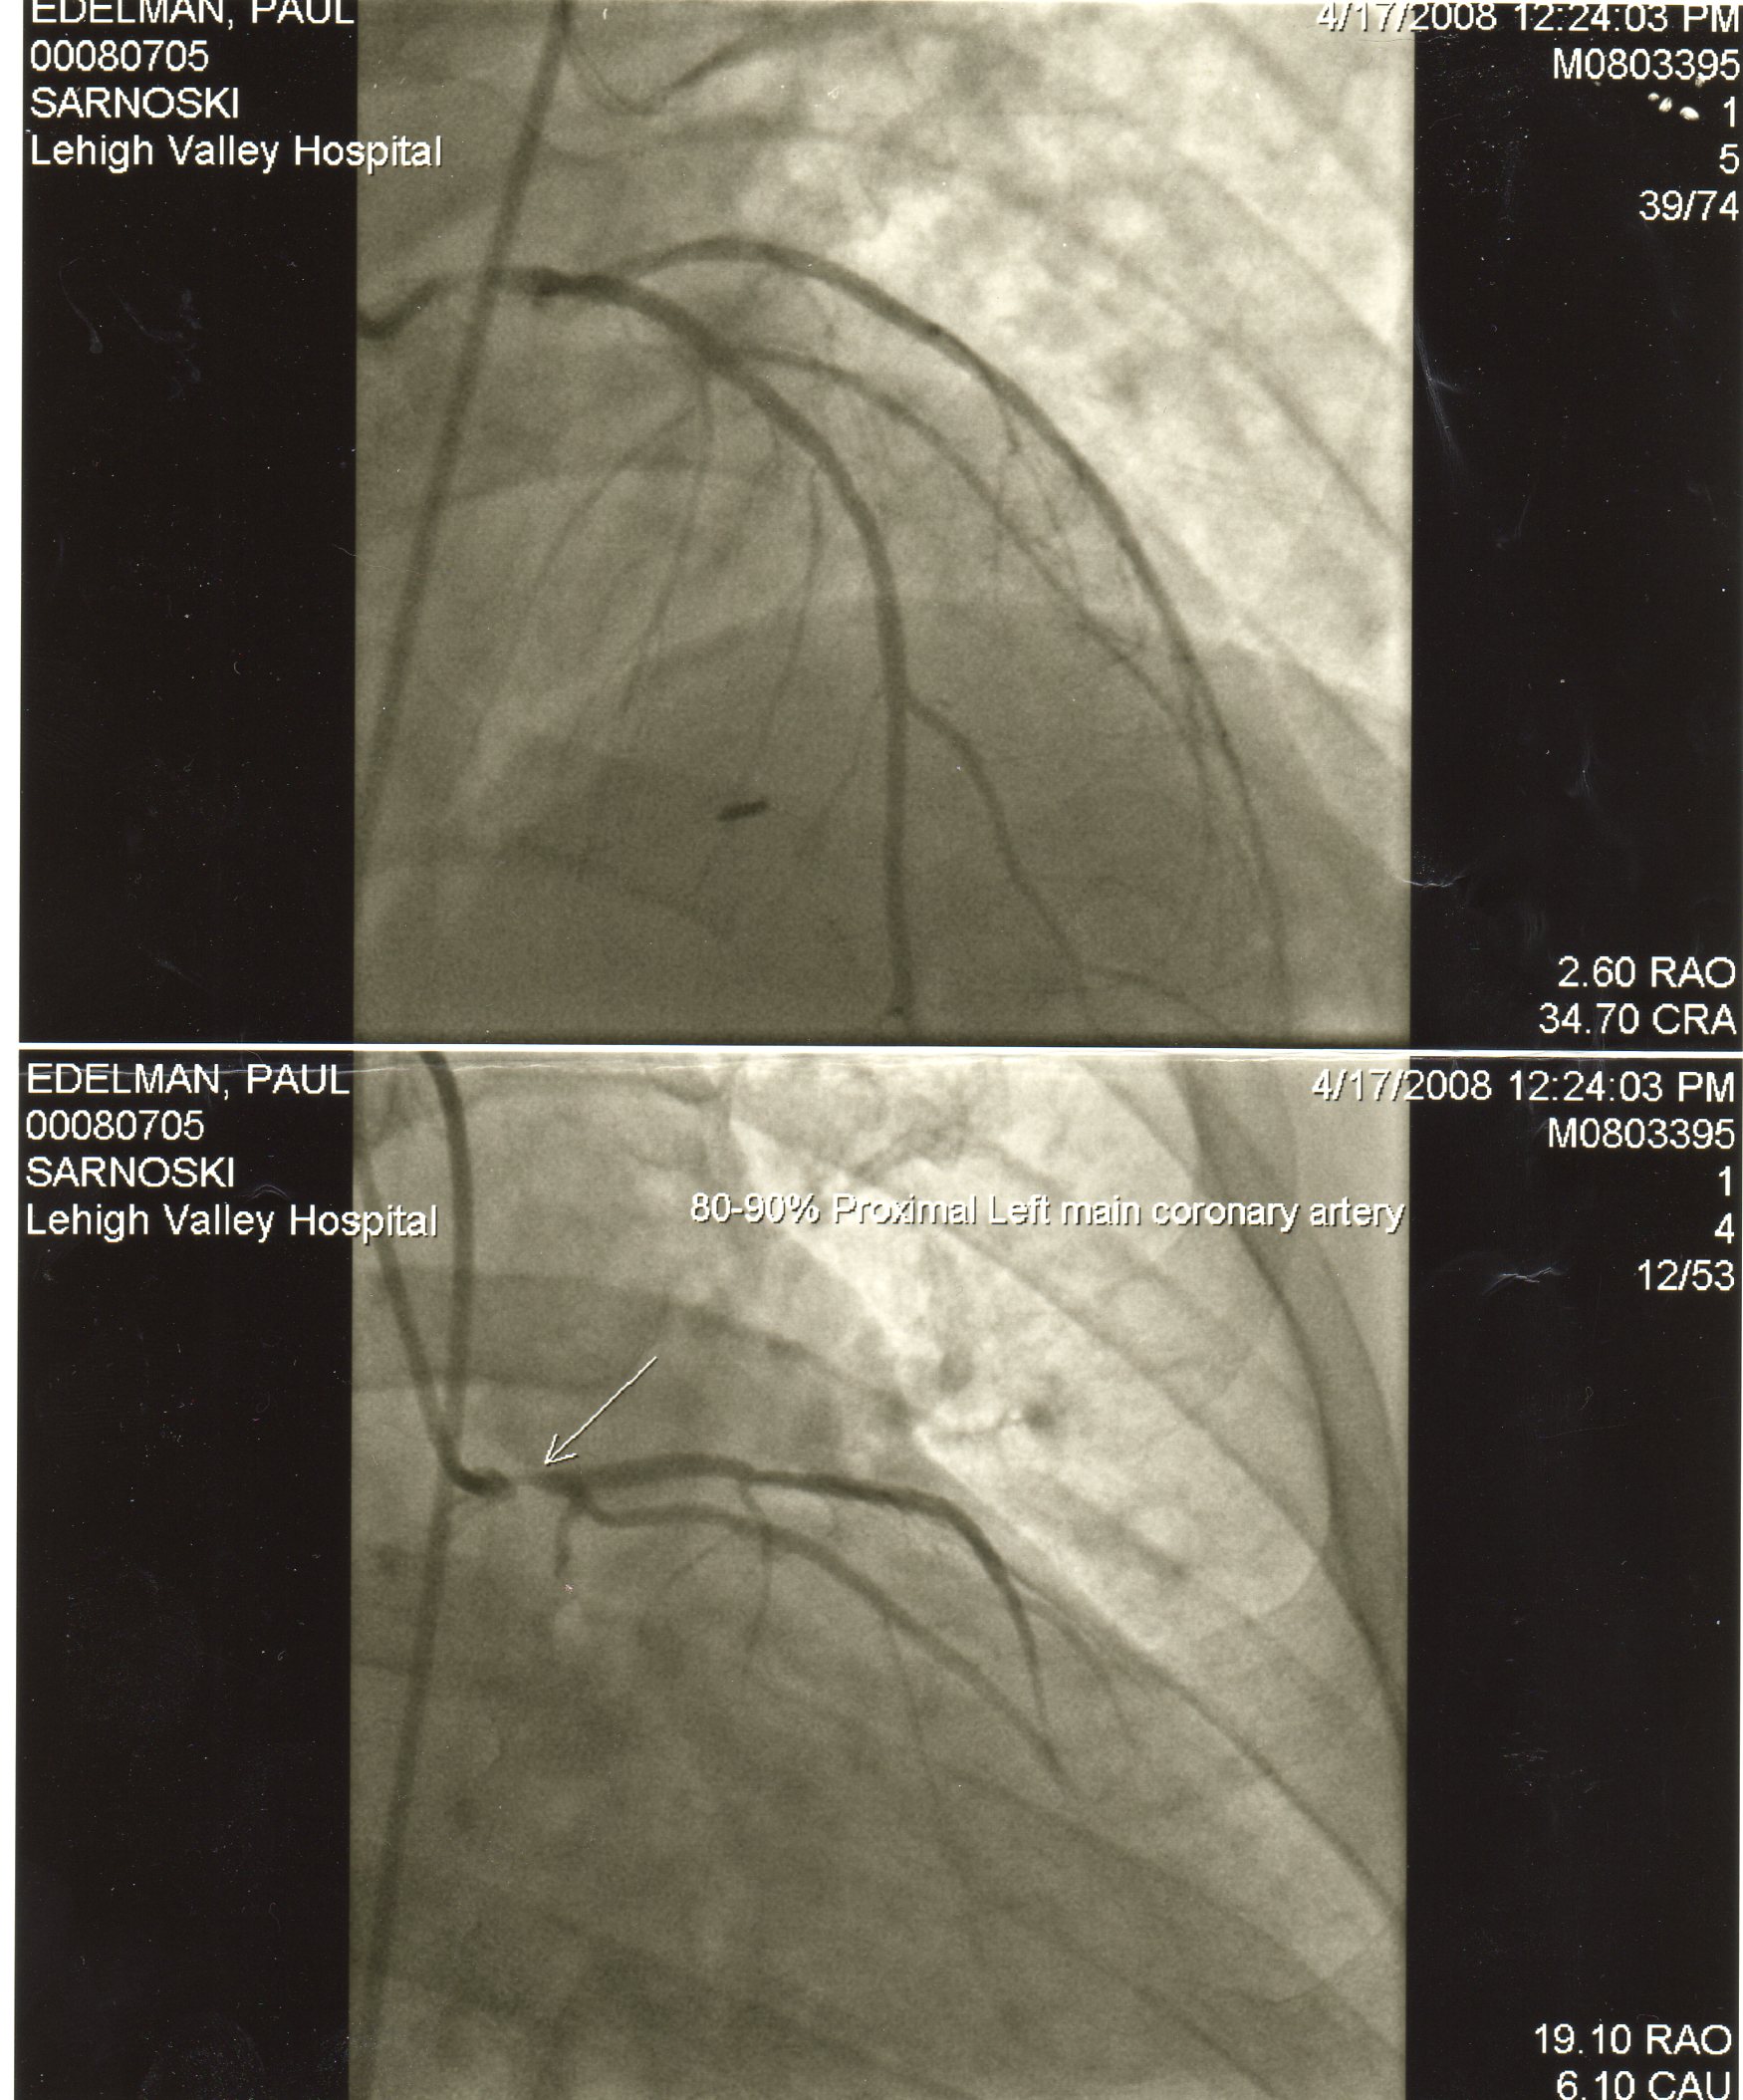

This is what my death looked like, or could have. You can see in the upper left corners of the two images, my name is spelled out. You can find out the details of this photo in the “Paul’s Heart” archives, under the post “Stress Kills.” The blockage which is quite visible is referred to in layman’s terms as a “widowmaker,” medically diagnosed as a blockage of the main artery going to the heart. Plainly put, you die from this, or at least, most do from a fatal heart attack. But this post is not about my death that almost was. This post is about what was going on before this picture was taken.

But as I mentioned, I was looking back in time, clearly for my LAD artery to be blocked 90%, it did not just occur over the four months that I felt something physical. Now to be fair, my cardiac condition is not the average overweight/out of shape blockage. Mine was due to over exposure of ionized radiation to my chest for my Hodgkin’s treatment. But that is also explained elsewhere in “Paul’s Heart”. But no matter the cause, stress has the potential to have long reaching effects, and perhaps fatal results. Looking back, I want to believe that I had my stress under control, and I want to believe that after my surgery I have my stress under control. The fact is, that I do not.

Recognize the triggers of the stress and you are half way to dealing with stress in a safer manner. Work, relationships, health, financial, schedule, life changes, all of these are bad enough individually let alone dealing with two or more. Personally, I am currently dealing with all six of these things on a very extreme level. And yes, in my mind, I have already plotted out all the worst case scenarios so that I am prepared for the worst if I have to deal with them, but I am also hoping for the best results which should in theory mean I will not subject my body to all the stressors that I am facing. After all, I have a proven track record, even in a picture of what stress can do. I showed you the picture at the beginning of what could have been a real bad ending. Now take a look at this picture. This is the one that saved my life.

These are actual photos of my heart, and the restriction of blood to my heart caused by the photo at the beginning. These were pictures taken during a “stress” test. First pictures were taken at rest, then you had pictures taken after a timed period on a treadmill that increased in speed and incline. My test did not last long as something showed up on the EKG after a minute and a half. Something was clearly wrong. And the picture showed, blood was not getting through my heart.

This was done on a treadmill. As I said, the feelings that I had came whether I was mowing the lawn, shoveling snow, at work, or even during a heated discussion. A sneezing fit could have caused enough physical stress at that point. As my cardiologist pointed out how lucky I was, “it wasn’t a matter of if I was going to have a fatal heart attack, but when.”